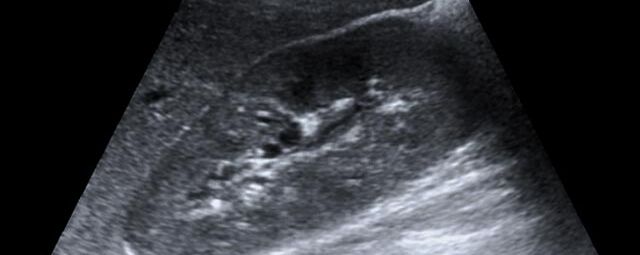

Die Sonographie ist ein bildgebendes Verfahren in der medizinischen Diagnostik, das mit Ultraschallwellen arbeitet. Ultraschall ist Schall mit einer Frequenz oberhalb der menschlichen Hörgrenze. Im medizinischen Bereich werden je nach Körperregion Ultraschallwellen in einem Frequenzbereich von ca. 3,5 – 18 Mhz verwendet. Die körpernahe Ultraschallsonde sendet durch einen piezoelektrischen Effekt kurze Schallwellenimpulse in den Körper. Ultraschall-Gel stellt den Kontakt zwischen Sonde und Körper her. Je nach Gewebeart werden diese Schallwellen im Körper unterschiedlich stark reflektiert. Anhand des zurückgesendeten Schallmusters kann das Ultraschallgerät Schnittbilder berechnen, auf denen die Organe des Körpers nach krankhaften Veränderungen untersucht werden können.

Der Arzt bewegt den Schallkopf mit leichtem Druck in verschiedene Richtungen. Die zu untersuchenden Strukturen können somit aus verschiedenen Perspektiven betrachtet werden. Aussagekräftige Bilder werden festgehalten und digital archiviert, Strukturen oder Organe können zusätzlich vermessen werden. Ein kurzes Befundgespräch erfolgt direkt nach der Untersuchung. Ihr zuweisender Arzt erhält von uns schriftlich einen ausführlichen Befundbericht.